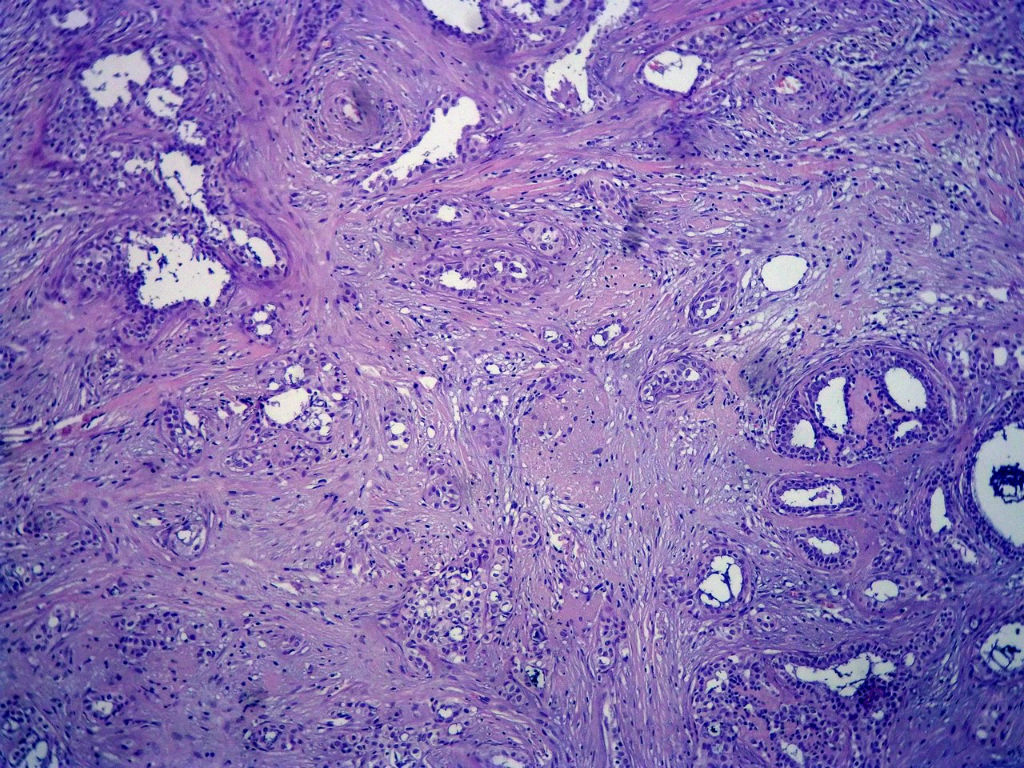

今天的一例术中冰冻。女,49岁,乳腺肿块。人气不旺,换个标题

腺病?癌?其他?(12楼常规,24楼免疫组化及会诊结果)图1

标签:浸润性导管癌 分泌癌 硬化性腺病

1. Most likely no invasive cancer

2 Sclerosing adenosis

3 Ductal epithelial hyperplasia

4. Bundles d Smooth muscle?

导管是乎可见双层上皮,部分上皮增生并有一定异型,考虑硬化性腺病,待石蜡。

导管可见双层上皮,部分上皮增生并有一定异型,考虑硬化性腺病

冰冻符合乳腺腺病

腺体与腺体之间的对比差异太大,不放心,不除外是癌,如果是我的病例,再次取材冰冻